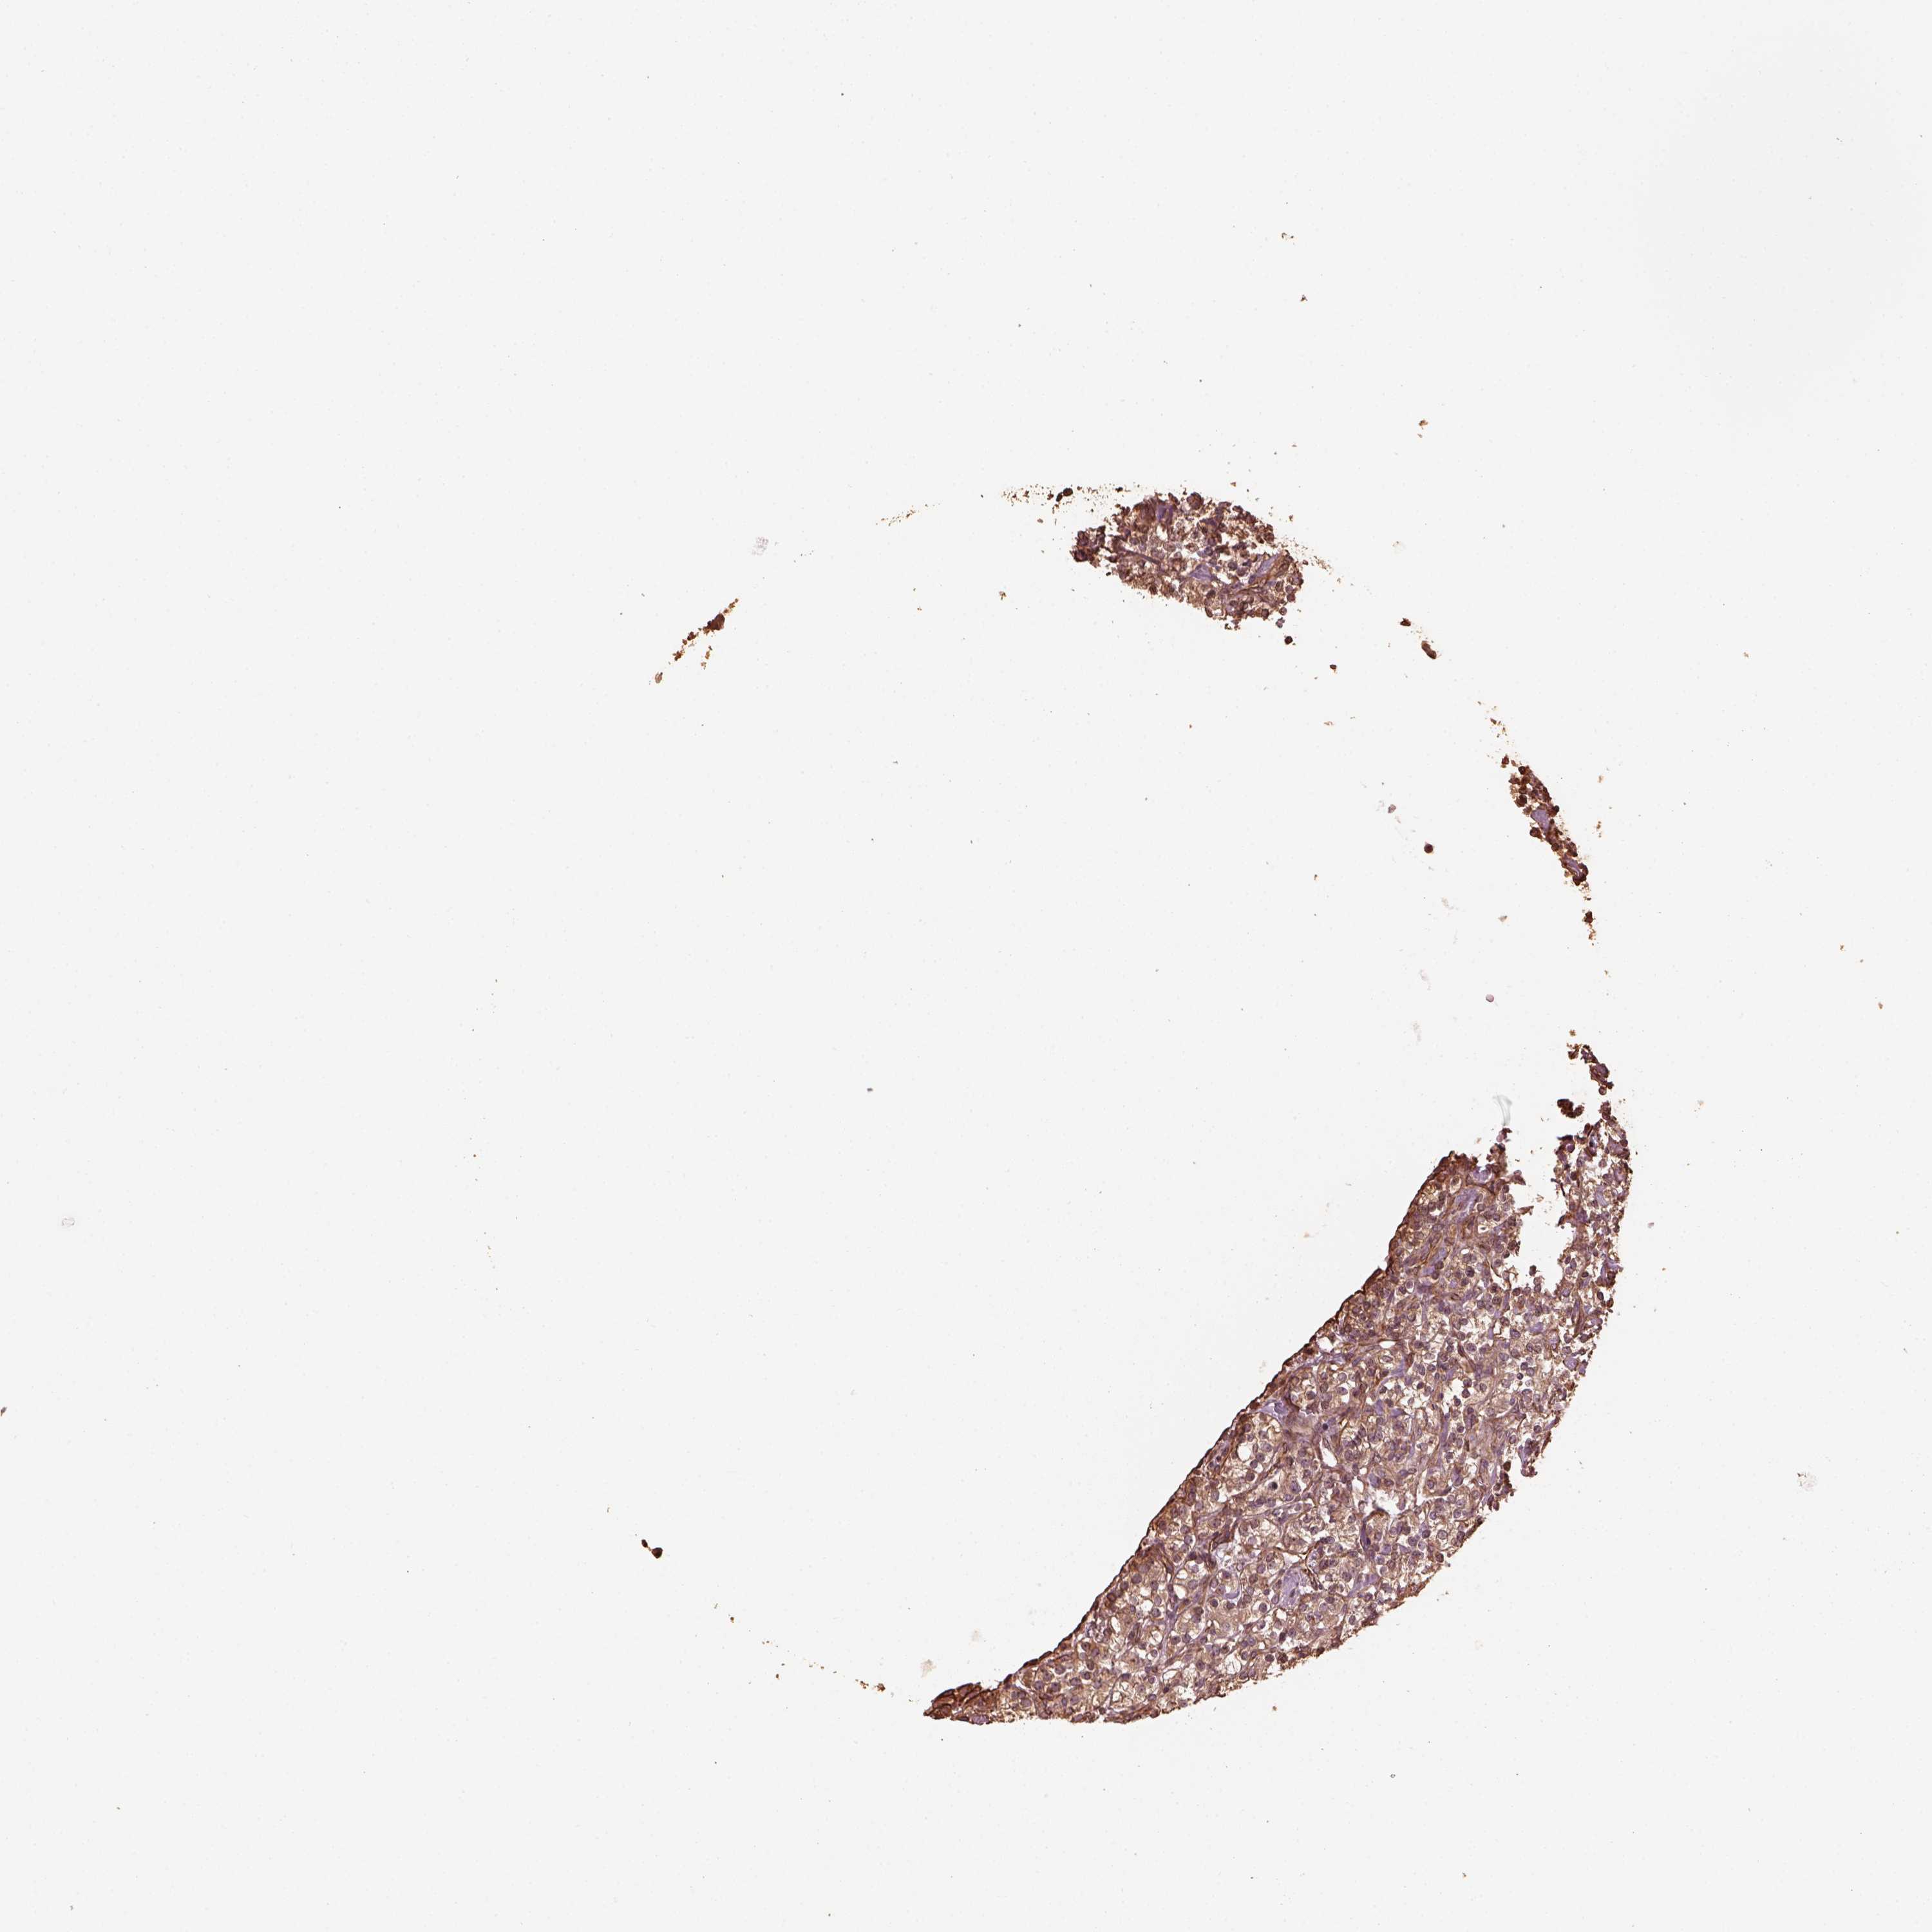

KIDNEY RENAL CLEAR CELL CARCINOMA (VALIDATION) - Interactive survival scatter ploti

The Survival Scatter plot shows the clinical status (i.e. dead or alive) for all individuals in the patient cohort, based on the same data that underlies the corresponding Kaplan-Meier plots. Patients that are alive at last time for follow-up are shown in blue and patients who have died during the study are shown in red.

The x-axis shows the expression levels (FPKM) of the investigated gene in the tumor tissue at the time of diagnosis. The y-axis shows the follow-up time after diagnosis (years). Both axes are complimented with kernel density curves demonstrating the data density over the axes. The top density plot shows the expression levels (FPKM) distribution among dead (red) and alive patients (blue). The right density plot shows the data density of the survived years of dead patients with high and low expression levels respectively, stratified using the cutoff indicated by the vertical dashed line through the Survival Scatter plot. This cutoff is automatically defined based on the FPKM cutoff that minimizes the p-score. The cutoff can be changed by dragging the vertical line or by entering a cutoff value in the square labeled "Current cut-off".

Under the Survival Scatter plot the p-score landscape (black curve; left axis) is shown together with dead median separation (red curve; right axis). Dead median separation is the difference in median mRNA expression between patients who have died with high and low expression, respectively. It is calculated as follows: median FPKM expression of dead patients with high expression - median FPKM expression of dead patients with low expression. This is intended to aid the user in visually exploring custom cutoffs and the associated p-scores and dead median separation.

Individual patient data is displayed and can be filtered by clicking on one or more of the category buttons on the top of the page. Categories describing expression level and patient information include: high, low, alive, dead, female, male and tumor stages. The scale of the x-axis can be toggled between linear and log-scale by clicking on the "x log" button. Mouse-over function shows TCGA ID, patient information and mRNA expression (FPKM) for each patient.

& Survival analysisi

Kaplan-Meier plots summarize results from analysis of correlation between mRNA expression level and patient survival. Patients were divided based on level of expression into one of the two groups "low" (under cut off) or "high" (over cut off). X-axis shows time for survival (years) and y-axis shows the probability of survival, where 1.0 corresponds to 100 percent.

GTPBP1 is not prognostic in Kidney Renal Clear Cell Carcinoma (validation)

Best expression cut offi

Based on the FPKM value of each gene, patients were classified into two groups and association between prognosis (survival) and gene expression (FPKM) was examined. The best expression cut-off refers the FPKM value that yields maximal difference with regard to survival between the two groups at the lowest log-rank P-value. Best expression cut-off was selected based on survival analysis .

When clicking on this number, the vertical dashed line indicating cut-off, the interactive survival plot, and the Kaplan-Meier curve will be adjusted to show results based on the best expression cut-off.

: 18.05

P scorei

Log-rank P value for Kaplan-Meier plot showing results from analysis of correlation between mRNA expression level and patient survival.

N/A

TCGA RNA samplesi

RNA-seq data is reported as average FPKM (number Fragments Per Kilobase of exon per Million reads), generated by the The Cancer Genome Atlas (TCGA) .

Normal distribution across the dataset is visualized with box plots, shown as median and 25th and 75th percentiles. Points are displayed as outliers if they are above or below 1.5 times the interquartile range. FPKM values of the individual samples are presented next to the box plot.

Average pTPM 19.7

Number of samples 100